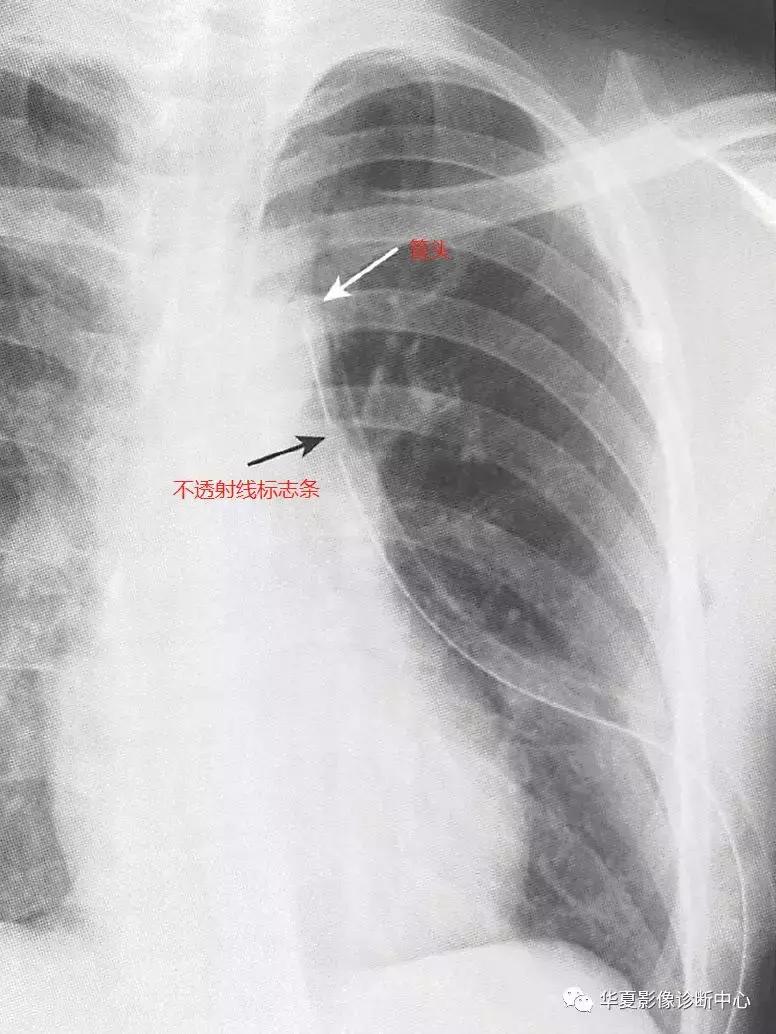

六、胸腔引流管

胸腔引流管是大口径导管,有一个在侧孔处中断的不透射线标志条,气胸引流的最佳位置是前上部,胸腔积液引流的最佳位置是后下部,胸腔引流管侧孔不应位于胸壁外,位置异常可导致引流不充分,当快速引流大量胸腔积液或气胸时,可引起复张性肺水肿。如果侧孔位于胸壁外,可导致引流不充分和胸壁皮下气肿。